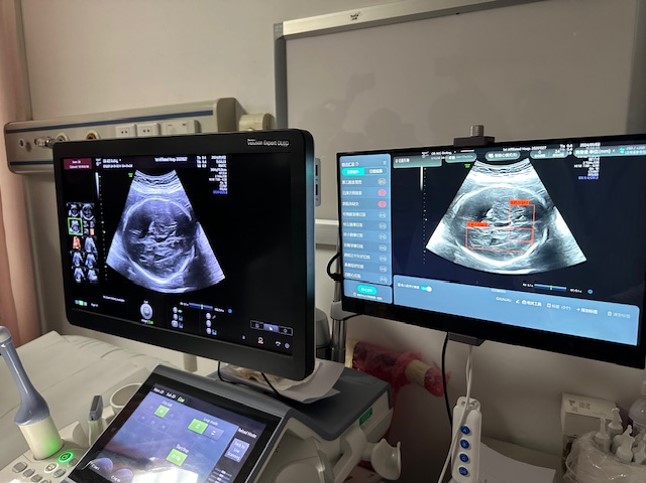

▲香港医疗人员到内地交流,了解当地先进治疗仪器及技术。 医管局提供

陈小强指,不少治疗程序都需要用上物理学家专长,如用作治疗和诊断的辐射、治疗癌症的电疗等。以肿瘤科为例,病人完成电脑扫描后,需要再勾划出肿瘤及正常细胞的分别,而内地的人工智能平均只需2、3分钟已可完成勾划,医生只需负责最后的检验和修改程序。他坦言,香港虽然也有采用人工智能技术,但多数以外国购入的软件进行,“而海外的软件多参照外国人的病例研发,而国内研发软件则以华人病例为本,模型准绳度可能较高。”他亦赞今次交流令两地医疗人员,能分享彼此技术的优劣之处,可望互补长短。